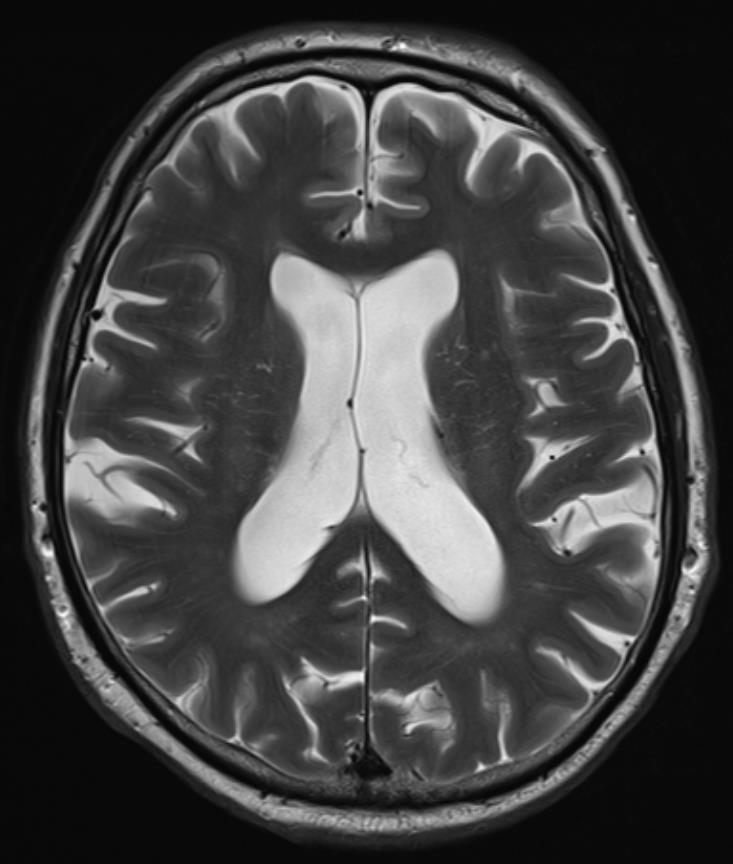

Deep Resolve is our AI-powered image reconstruction technology for MRI

• Enabling faster acquisitions, increased clinical productivity and better patient experience

• Increased image quality and resolution

• Reduced energy consumption per acquisition 2x

- Abnormality detection, acute infarction, acute hemorrhage, mass effect

Sagittal T1W, FLAIR, TraceW, & ADC

Processing mpMRI data after repositioning via landmarks & skull stripping

AI system

Trained on 25,000 MRI studies